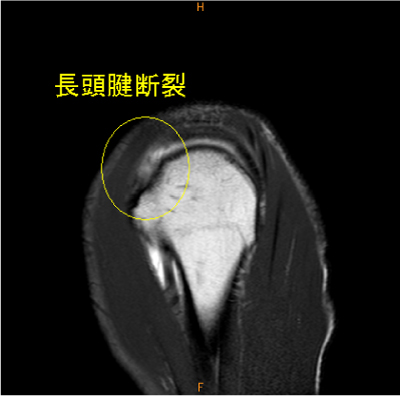

MRI所見

長頭腱の不全断裂は稀な所見である。

MR関節造影で無かったら、描出されて無かった可能性が高い。上方関節唇損傷も認めている。

長頭腱の不完全断裂